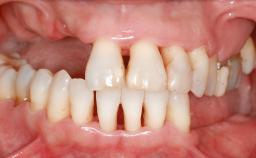

An 18-year-old man was referred for implant therapy in the posterior mandible to the Department of Oral Surgery and Stomatology (University of Bern, Switzerland). He was healthy and did not smoke. Tooth 35 was congenitally missing, involving a single-tooth edentulous space that offered an adequate mesiodistal dimension for implant placement but exhibited a typical pattern of buccal flattening. A panoramic radiograph was obtained, which revealed a sufficient vertical bone height above the mandibular canal and a normal bone structure in the edentulous area.

Soft Tissue Anatomy Intact Defective

Bone Volume Horizontally and vertically sufficient Horizontally deficient Deficient vertically or deficient vertically AND horizontally